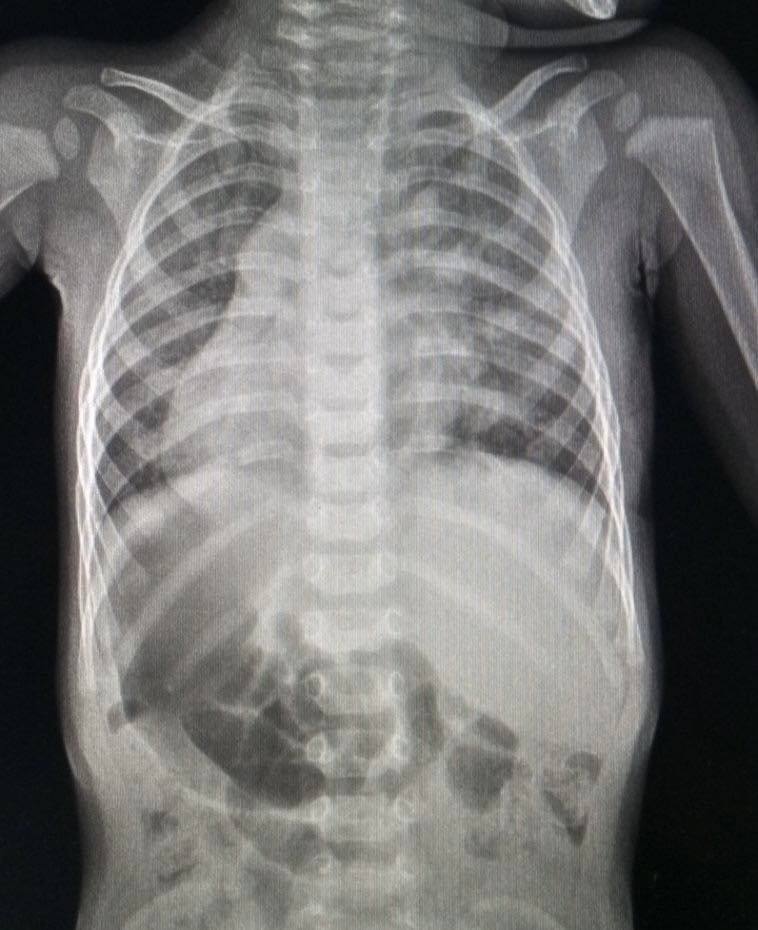

Ця історія — не просто медичний кейс, а приклад того, як сучасна українська кардіохірургія дозволяє виправляти найскладніші помилки природи. Малюк народився з situs inversus — станом, при якому внутрішні органи розташовані нетипово. Сама по собі ця особливість не є хворобою, але в даному випадку вона супроводжувалася критичним дефектом, який виявили лише під час планового обстеження.

Дзеркальне розташування органів зустрічається приблизно у однієї людини на десять тисяч. Для хірургів це завжди додатковий рівень складності, адже вся звична «карта» людського тіла стає перевернутою. Коли малюку виповнилося 9 місяців, фахівці виявили складну вроджену ваду серця.

Мова йде про дефект міжпередсердної перегородки з аномальним дренажем легеневих вен. Простіше кажучи, кров у серці маленького закарпатця циркулювала неправильно, що створювало колосальне навантаження на легені та серцевий м’яз. Без термінового втручання малюк міг отримати незворотні зміни в організмі вже до двох років.